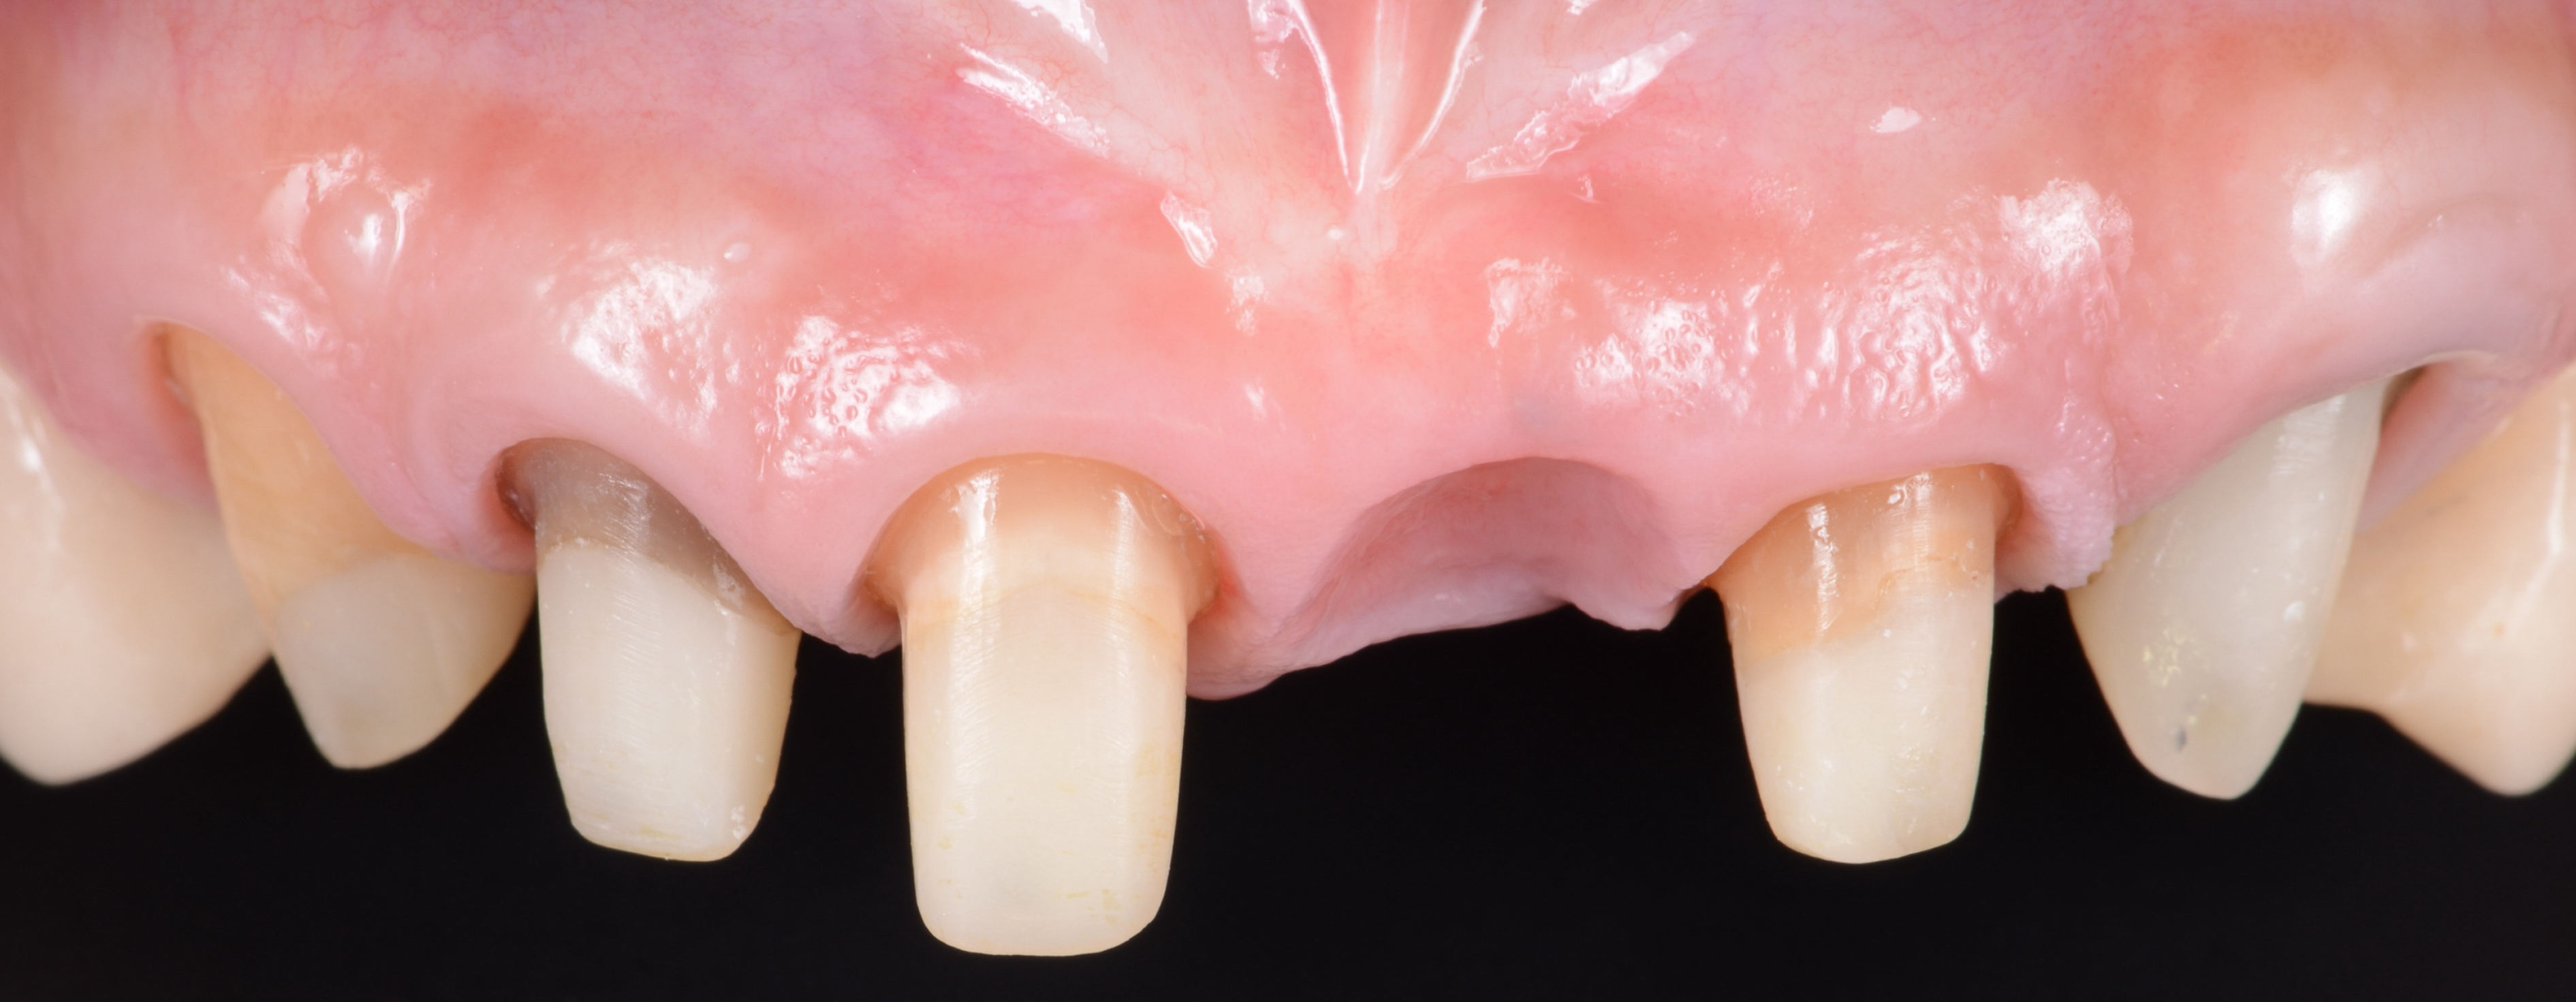

FGG(遊離歯肉移植術)で歯肉増大と歯の根元を被覆した症例

根面被覆術で歯肉退縮を改善した症例